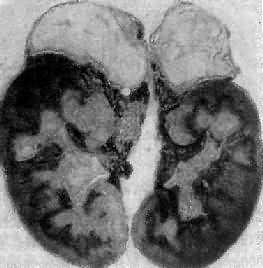

图15-15 双侧肾上腺结核

二、肾上腺皮质功能低下(一)急性肾上腺皮质功能低下症 急性肾上腺皮质功能低下症(acute adrenocortical insufficiency)的病因主要有①皮质大片出血、双侧肾上腺静脉血栓形成,多为败血症的合并症,可能由于毒素损伤了血管,或者由于DIC所致;②在慢性肾上腺皮质功能低下的基础上,由于重症感染、外伤引起了应激反应;③长期皮质激素治疗后突然停药。临床出现血压下降、休克、昏迷等症状,严重时可致死亡。 (二)慢性肾上腺皮质功能低下症 本病又称Addison病,乃由两侧肾上腺皮质严重破坏所致,当破坏超过90%时才出现临床症状,否则为亚临床型。发病呈隐匿性,主要症状是皮肤和粘膜以及瘢痕处的黑色素沉着增加,这是由于肾上腺皮质激素减少,促进垂体ACTH及β-LPH分泌增加,而ACTH及β-LPH在氨基酸排列顺序上有相当一部份与α或β黑色素细胞刺激素(α-MSH、β-MSH)氨基酸顺序相同,故有MSH活性(成人垂体不合成MSH),促进黑色素细胞制造黑色素。由于ACTH分泌不足而导致的继发性肾上腺皮质功能低下时无黑色素沉着,可与本症相鉴别。此外还有低血糖、低血压、肌力低下、易疲劳、食欲不振、体重减轻等症状。 引起本病的病因主要有双侧肾上腺结核(图15-15)和特发性肾上腺萎缩,偶尔也可因转移癌引起。特发性肾上腺萎缩(idiopathic adrenal atrophy)是自家免疫性炎症,故又称自家免疫性肾上腺炎(autoimmue adrenalitis),多见于青年,女性显著多于男性。病人血中常有抗肾上腺皮质细胞线粒体或微粒体抗体,常与其他自家免疫性疾病合并。双侧肾上腺高度萎缩,共重2.5g以下;皮质菲薄,镜下除皮质萎缩外,有大量淋巴细胞和浆细胞浸润。